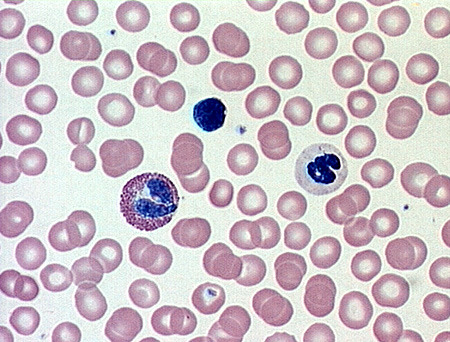

blood

Only fluid tissue of the body; transport